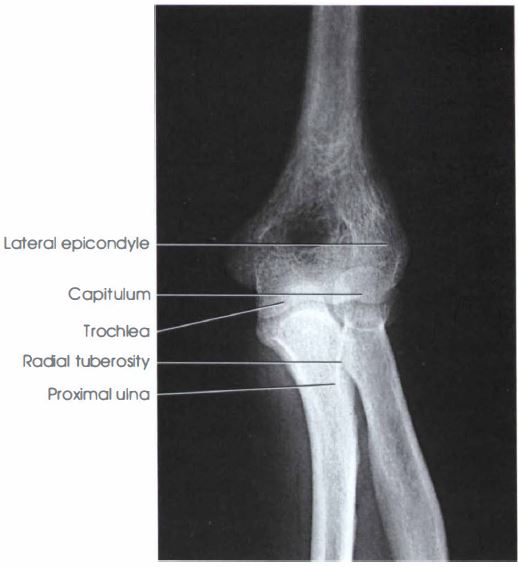

Title : Labeled Elbow Xray Anatomy Ap View Anatomy Radiology Elbow Xray Ap Source : www.grepmed.com Open New Window